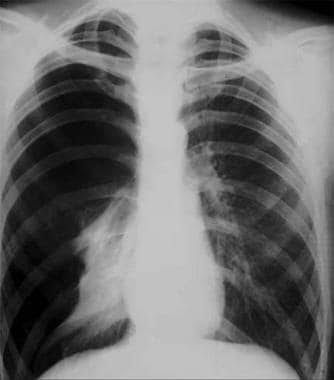

A pneumothorax (noo-moe-THOR-aks) is a collapsed lung. A pneumothorax occurs when air leaks into the space between your lung and chest wall. This air pushes on the outside of your lung and makes it collapse. A pneumothorax can be a complete lung collapse or a collapse of only a portion of the lung.